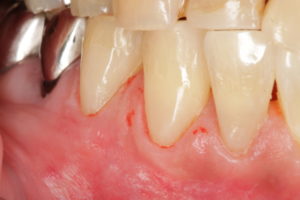

合計3本ですが、1時間30分かかってます。写真で見てこのレベルまで仕上げれば、肉眼ではよく目を凝らさないと詰め物は見えません。私も、肉眼ではわかりません。3.6倍のルーペを使って治療してます。